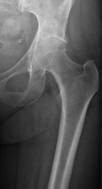

Τα τελευταία χρόνια δυναμικά στο προσκήνιο μπαίνουν οι εγχειρήσεις μικρής επεμβατικότητας, δηλαδή με μικρές τομές και προσπελάσεις. Η ΑΜΙS (αρθοπλαστική μικρής επεμβατικότητας) είναι μέθοδος με πολύ μικρή τομή ( μικρότερη των 10 εκατοστών) χωρίς τομή μυών ή τενόντων όπως στην κλασσική επέμβαση. Έτσι η μετεγχειρητική νοσηλεία είναι πολύ ελαφρύτερη, με σπάνιες επιπλοκές, ελάχιστες μεταγγίσεις και πολύ γρήγορη κινητοποίηση, από την 2η ημέρα.

Η ΑΜΙS είναι εξαιρετική επιλογή στη θεραπεία οστεοαρθρίτιδας του ισχίου, δεν μπορεί όμως να εφαρμοστεί σε όλους τους ασθενείς (σωματότυπος). Απαιτεί ειδικά εργαλεία κι εκπαιδευμένη στη μέθοδο χειρουργική ομάδα.